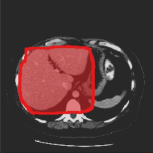

Consider a three-dimensional object within a volume. It is straightforward to produce a 3D bounding box of the object by finding its extreme points in the three coordinate axes. While this 3D bounding box will be tight in the 3D sense, its rectangular cross-sections will not, in general, remain tight with respect to the planar cross-sections of the volume. Fig. 1 illustrates such a case for the task of liver segmentation in a CT volume. In the Experiments section we show that the success of existing 2D weakly-supervised segmentation methods relies on the bounding boxes being tight and therefore the tightness of the individual 2D bounding boxes should be corrected before training and applying a segmentation CNN.

(a)

(b)

(c)

(d)

The global bounding box tightness prior mentioned above assumes that each of side of the box is sufficiently close to the target region. This means that for any region shape, each vertical or horizontal line inside the bounding box will cross at least one pixel belonging to the target region. This condition does not hold when the provided annotation comes as a 3D bounding box which is represented as a series of per-slice non-tight 2D bounding boxes. In this case, there will exist vertical or horizontal lines shown as stripes in Fig. 1 (d), that will lie outside of the actual object boundary. In the Experiments section we demonstrate the poor performance of the weakly-supervised approach from [5] when the user-provided bounding box is much wider than the true object of interest.